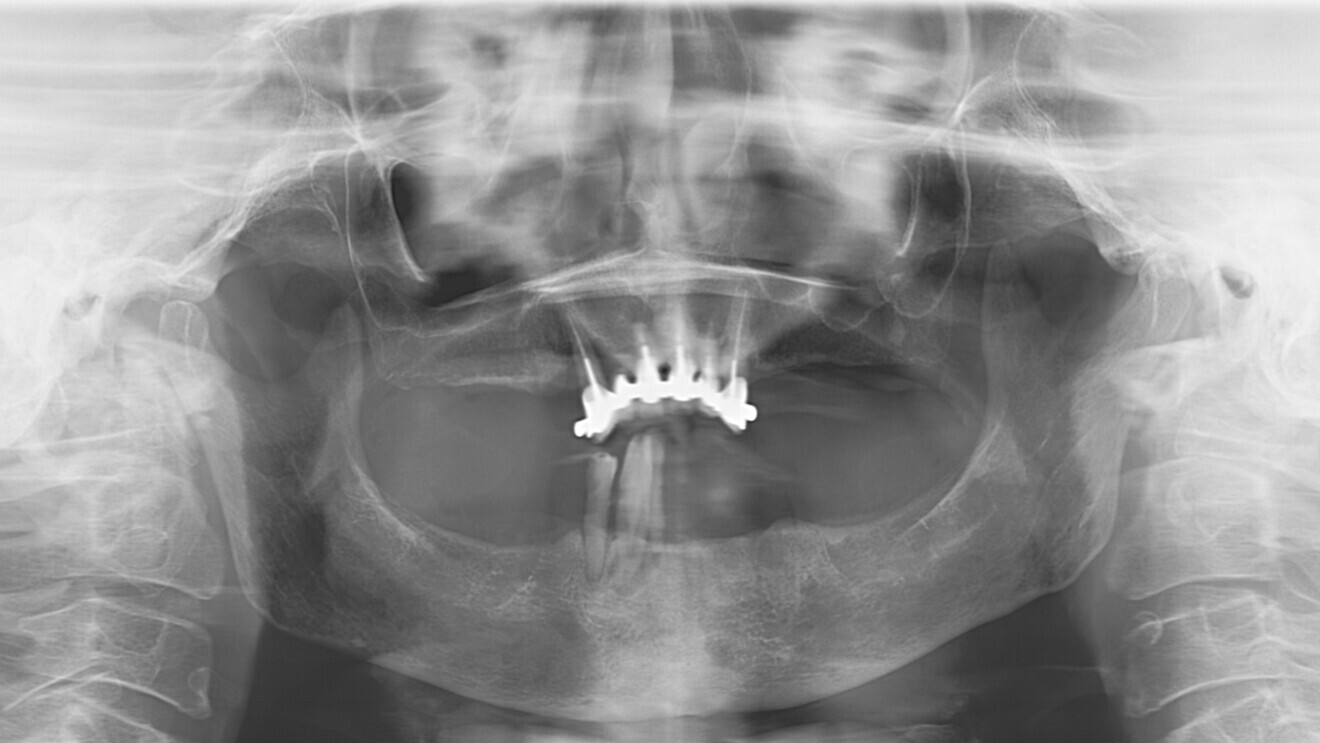

L’évaluation clinique a révélé un manque de soutien dentaire pour la lèvre inférieure et une récession gingivale significative autour du bridge maxillaire et des trois dents mandibulaires résiduelles (Figs. 1 et 2). Après examen clinique et radiologique (Figs. 3 et 4), la décision de réalisation d’une prothèse complète maxillaire et d’une réhabilitation fixe mandibulaire par implants est prise en accord avec la patiente.

Fig. 3 : Orthopantomogramme de la situation clinique.